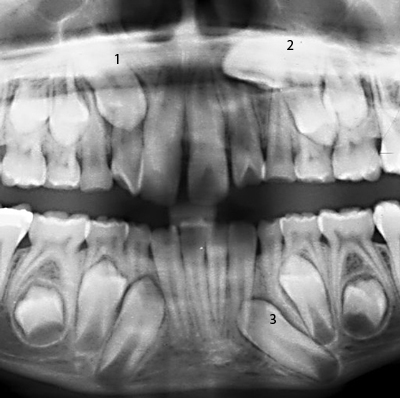

Puppy Teeth Xray Pictures

The Importance Of Dental Radiographs Hillcrest Animal Hospital